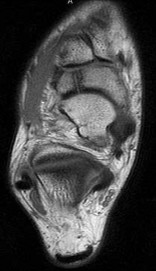

A 55-year-old woman feels a 'pop' in the back of her knee while squatting. An MRI is shown:

A posterior horn medial meniscus root tear is identified. Biomechanically, a complete medial meniscus posterior root tear alters contact pressures to a degree equivalent to which of the following?

Explanation

A complete posterior root tear of the medial meniscus leads to a complete loss of hoop stresses, resulting in meniscal extrusion. Biomechanically, this alters peak tibiofemoral contact pressures and reduces contact area to a degree equivalent to a total meniscectomy, leading to rapid articular cartilage degeneration.